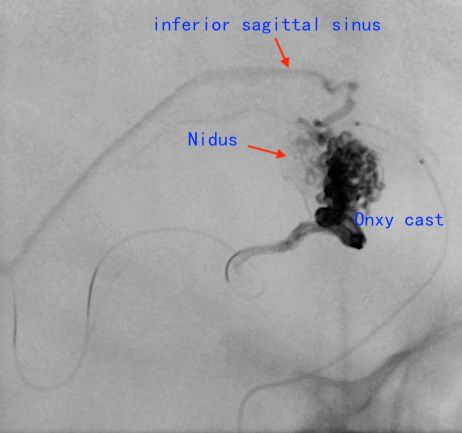

图2:右侧颈内动脉造影,右侧胼胝体动静脉畸形,供血动脉为胼周动脉供应胼胝体动脉分支,引流静脉通过透明隔静脉向大脑内静脉引流及通过下矢状窦向直窦引流红色箭头为供血动脉,蓝色箭头为引流静脉。

全麻插管,右侧股动脉置6F鞘,右侧颈内静脉置5F鞘。右侧颈内动脉放置6F导引导管,路图下,在Traxcess14微导丝导引下把Scepter 4*10球囊放置在畸形血管团供血动脉处,充盈球囊,造影,见畸形血管团不显影。然后通过颈静脉鞘,5F125cmsofia导引导管在marathon和Traxcess14导引下超选至直窦,marathon在Traxcess14导引下超选至畸形血管团静脉起始段内。充盈Scepter球囊,marathon静脉内造影,造影剂淤滞,予以充盈球囊后通过静脉内注胶,但发现胶依然快速向静脉移位,考虑仍有供血动脉球囊仍未完全覆盖,调整球囊并通过球囊导管造影发现该畸形血管团由相对独立两部分组成。重新调整球囊并完全覆盖供血动脉后再次通过静脉内注Onyx胶,较弥散良好。但因畸形血管团由两个相对独立部分组成,胶未能弥散另一部分畸形血管团内,予以通过球囊导管动脉入路栓塞,Scepter球囊导管超选供血动脉,予以16.6%GLUBRAN胶栓塞,造影见畸形血管团完全治愈性栓塞,术中控制性降压(比打胶前将低20mmHg),并中和肝素术后CT未见出血,术后患者清醒,功能无障碍。